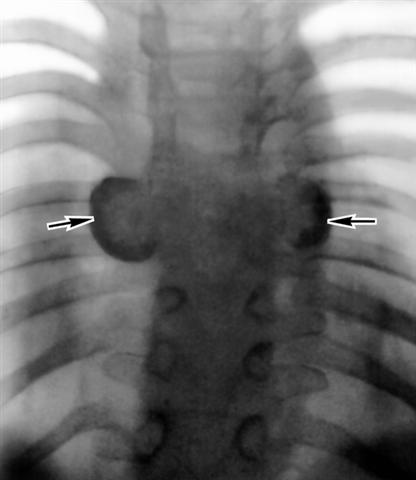

Рис. 3. Рентгенограмма среднегрудного отдела позвоночника при туберкулезном спондилите (переднезадняя проекция): позвоночник деформирован, с обеих сторон к нему прилежат шаровидные натечные абсцессы (указаны стрелками).